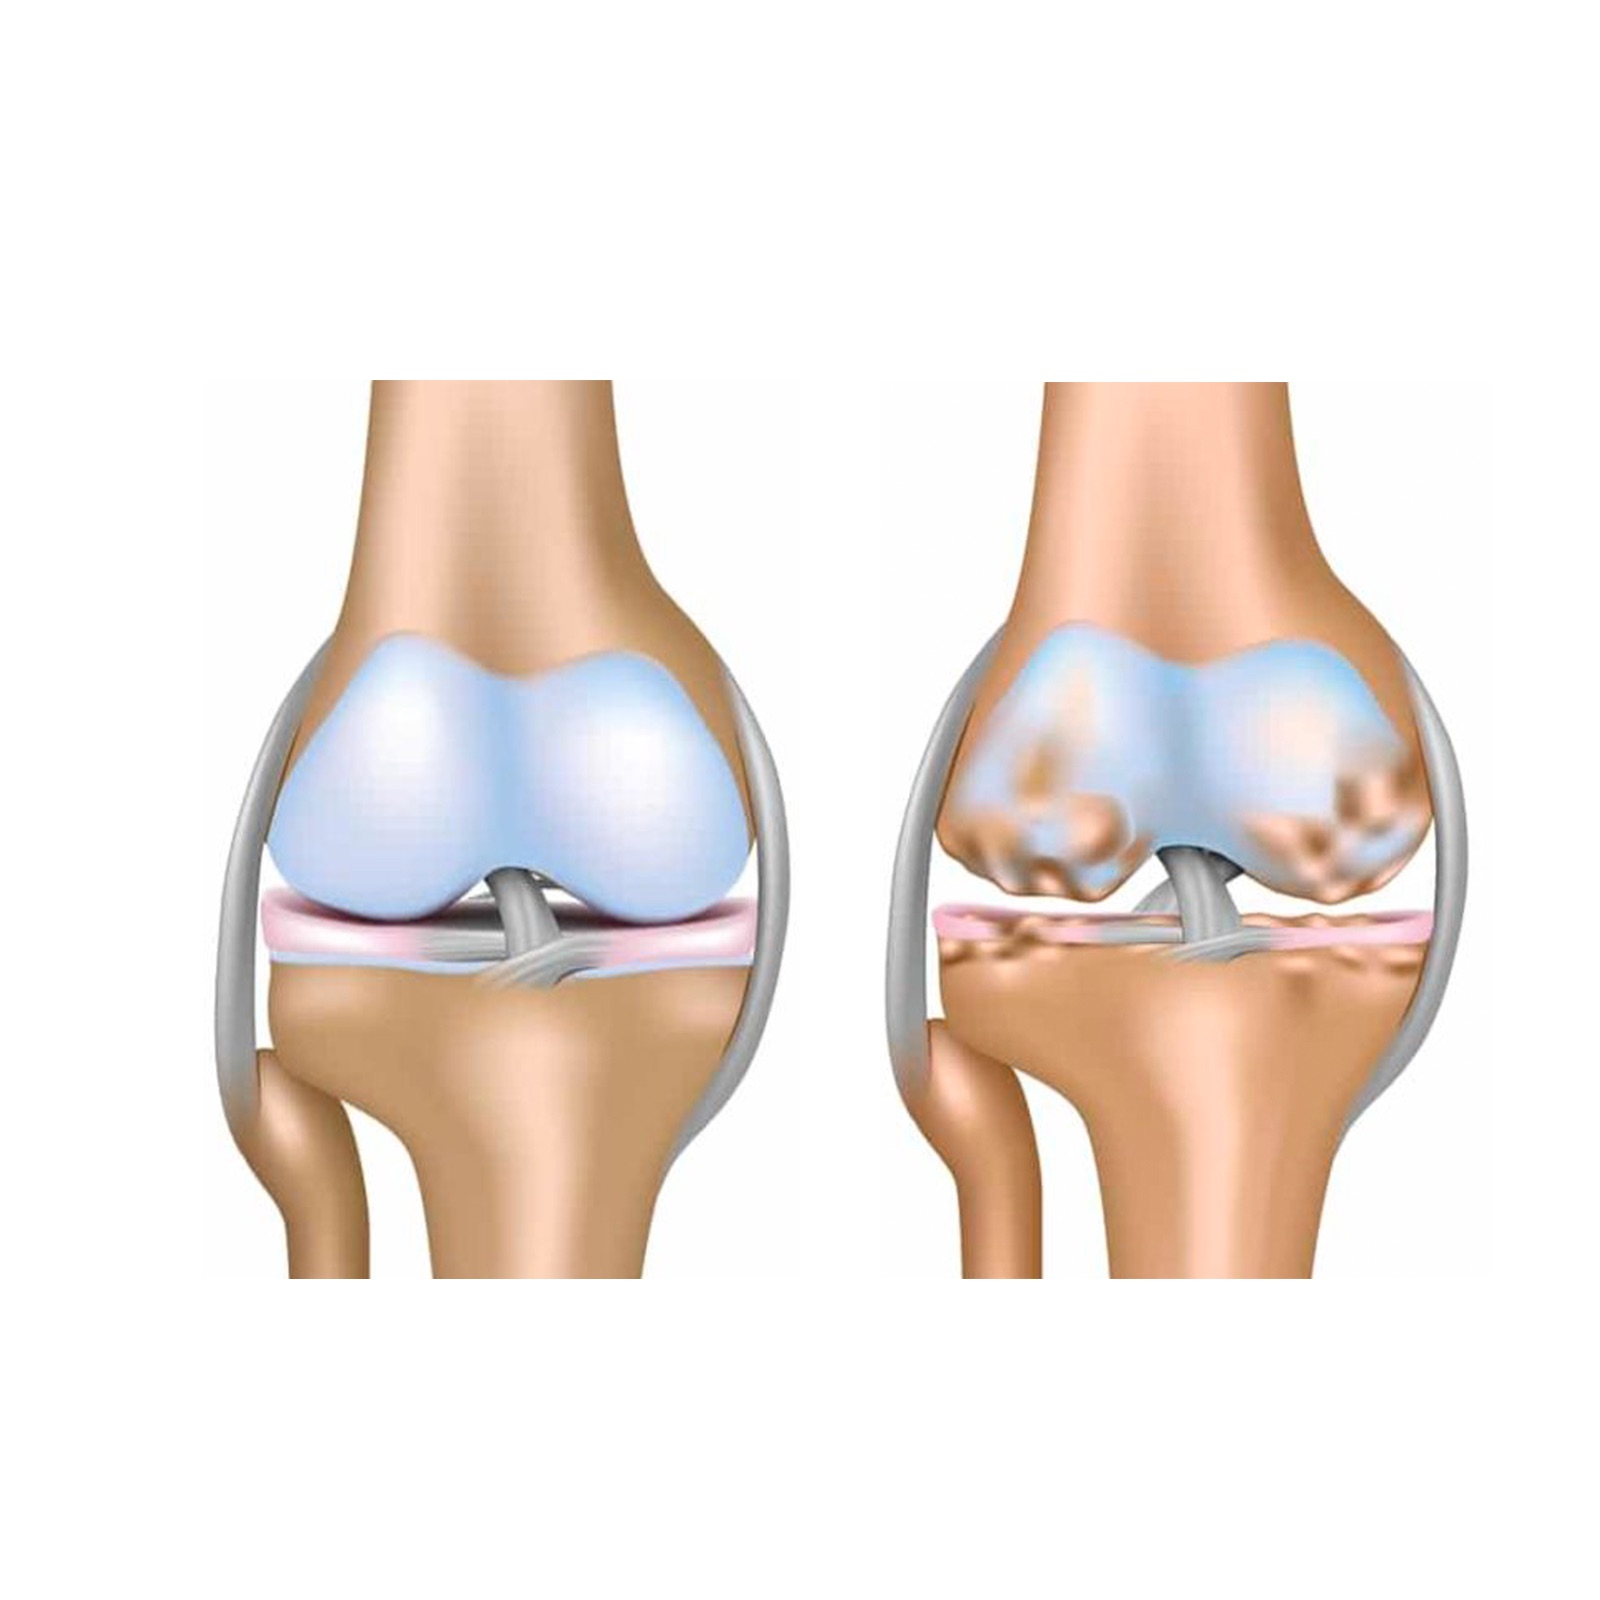

Некроз тазобедренного сустава: Фотографии и особенности лечения